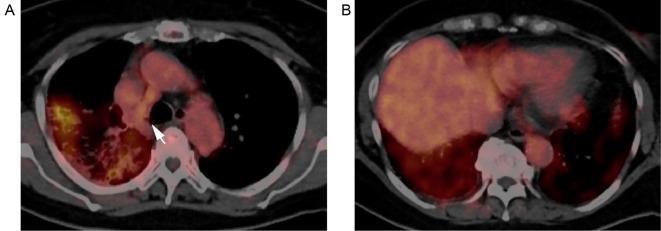

Mesenchymal-epithelial transition (MET) exon 14-skipping mutation (METex14) is rare in pulmonary invasive mucinous adenocarcinomas (IMAs), and the clinical impact of MET-tyrosine kinase inhibitors (TKIs) remains unknown. We herein report a 75-year-old woman with IMA harboring METex14 who was treated with the MET-TKI tepotinib. The lung tumor regressed over six months; however, the patient ultimately died of exacerbated interstitial lung disease (ILD), possibly associated with tepotinib. An autopsy revealed diffuse alveolar damage in pre-existing chronic fibrosis. We discuss how to pre-evaluate ILD deterioration risks and monitor TKI-induced lung toxicity during treatment.

间质上皮转化(MET)外显子 14 跳跃突变(METex14)在肺浸润性黏液腺癌(IMAs)中较为罕见,MET 酪氨酸激酶抑制剂(TKIs)的临床影响尚不清楚。本文报告了一例 75 岁女性肺 IMAs 合并 METex14,接受 MET-TKI 特泊替尼治疗。肺肿瘤在六个月内消退;然而,患者最终死于加重的间质性肺病(ILD),可能与特泊替尼有关。尸检显示,在先前存在的慢性纤维化中存在弥漫性肺泡损伤。我们讨论了如何在治疗前评估ILD 恶化风险和监测 TKI 诱导的肺毒性。